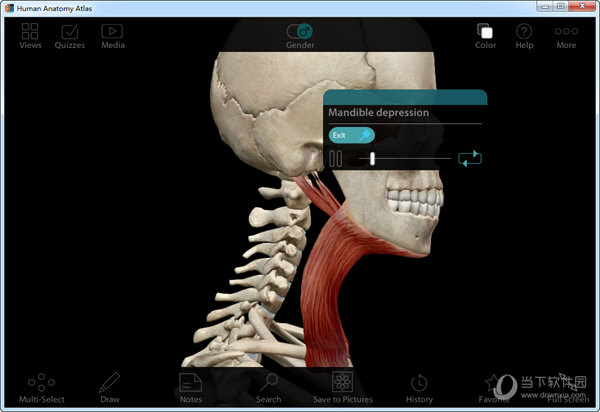

5、支持隐藏或淡入淡出多个结构

6、支持访问视图,收藏夹,测验和动画

3、通过滚轮实现放大缩小,也可通过右上角的放大功能进行单个部位放大。